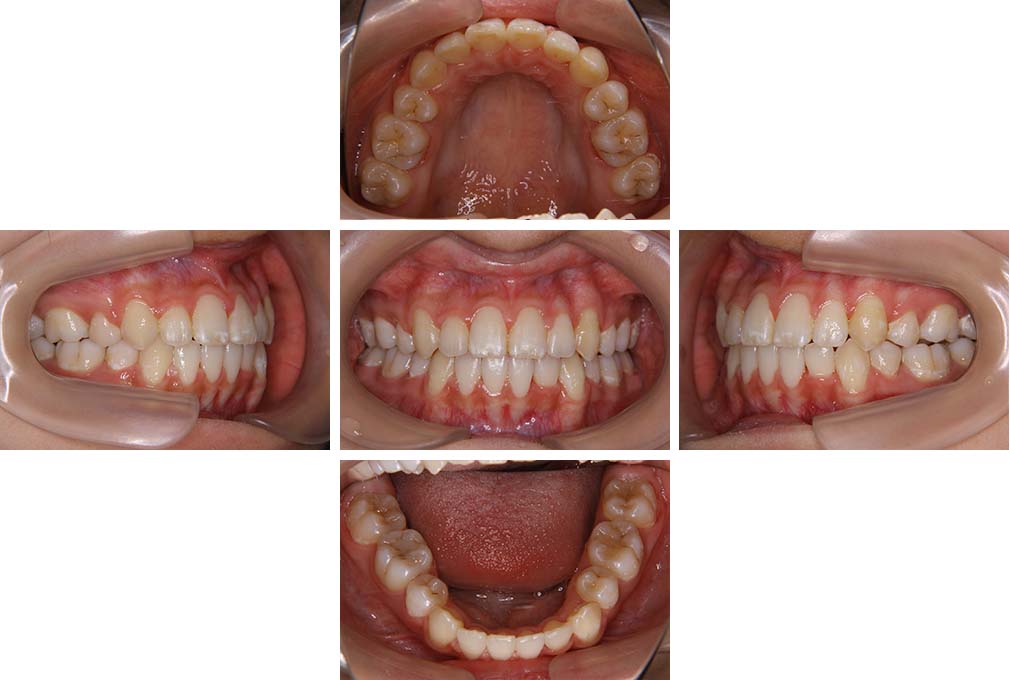

CASE:03

上下顎前突

初診時年齢 18歳4か月

性別 男性

治療費の目安 105万円程度(治療開始時)

歯列の乱れは著しくなく上顎右側側切歯が捻転し口蓋側へ転位していた。また、問診の中で患者さんから最も重視する治療結果として口元の突出の改善の申出があった。下顎が後退した上顎前突傾向ではあったが著しいものではなかった。上下顎前突と診断し上下顎小臼歯抜歯を行っていただき、上下顎舌側マルチブラケット装置を使用して、矯正用アンカースクリューを併用して動的治療を行った。上下顎前歯の後退を十分行い口元の突出感も改善した。治療後10年1か月の来院時には口元の突出感が再発することもなく、下顎前歯の少しの唇舌的なずれはあったが歯列は安定していた。動的治療期間2年2ヵ月間。

治療前

18歳4ヵ月

治療後

動的治療期間2年2カ月間

20歳10か月

10年経過

動的治療終了後10年1カ月

30歳11か月